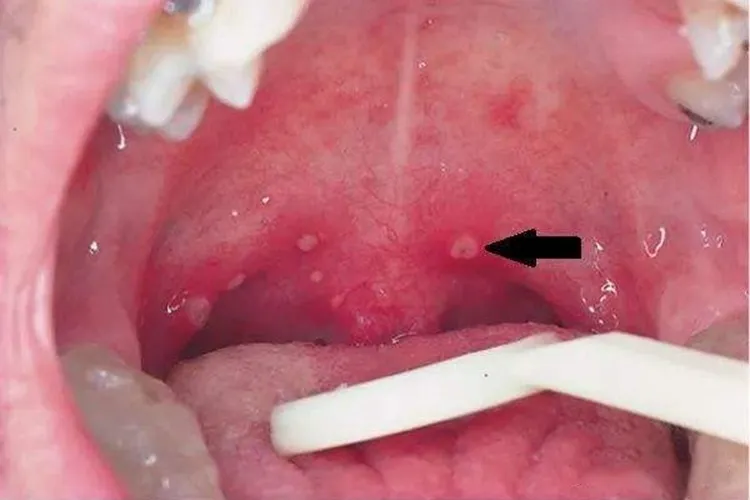

口腔黏膜疹:早期出现,类似粟粒样斑丘疹或水疱,周围有红晕。口腔里的小水疱常长在硬腭、颊部、牙龈、舌头等处,患儿会自觉疼痛,并且水庖容易破溃。